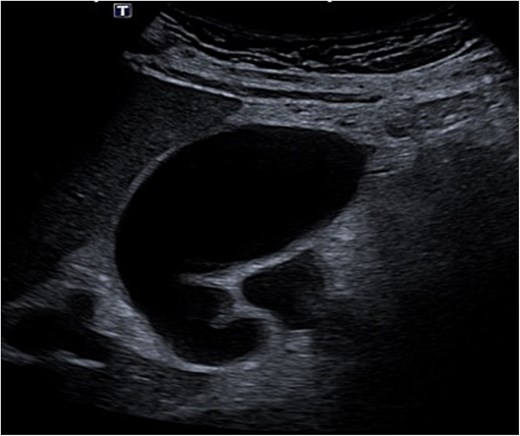

Despite the absence of abdominal symptoms, a computed tomography of the abdomen and pelvis (CTAP) was performed due to markedly elevated lipase levels. The CTAP (Figs 3–5) revealed evidence of acute pancreatitis (Fig. 5, arrow), with a complex peripancreatic fluid collection (Fig. 3, arrow). Additionally, a focal thrombus was observed within the portal venous confluence (Fig. 4, arrow). Further ultrasound of the gallbladder was negative for gallstones (Fig. 6), ruling out gallstone-induced pancreatitis.

CTAP coronal view; complex peripancreatic fluid collection (arrow) with extension behind the splenic vein to lie adjacent to the pancreatic neck and uncinate process.